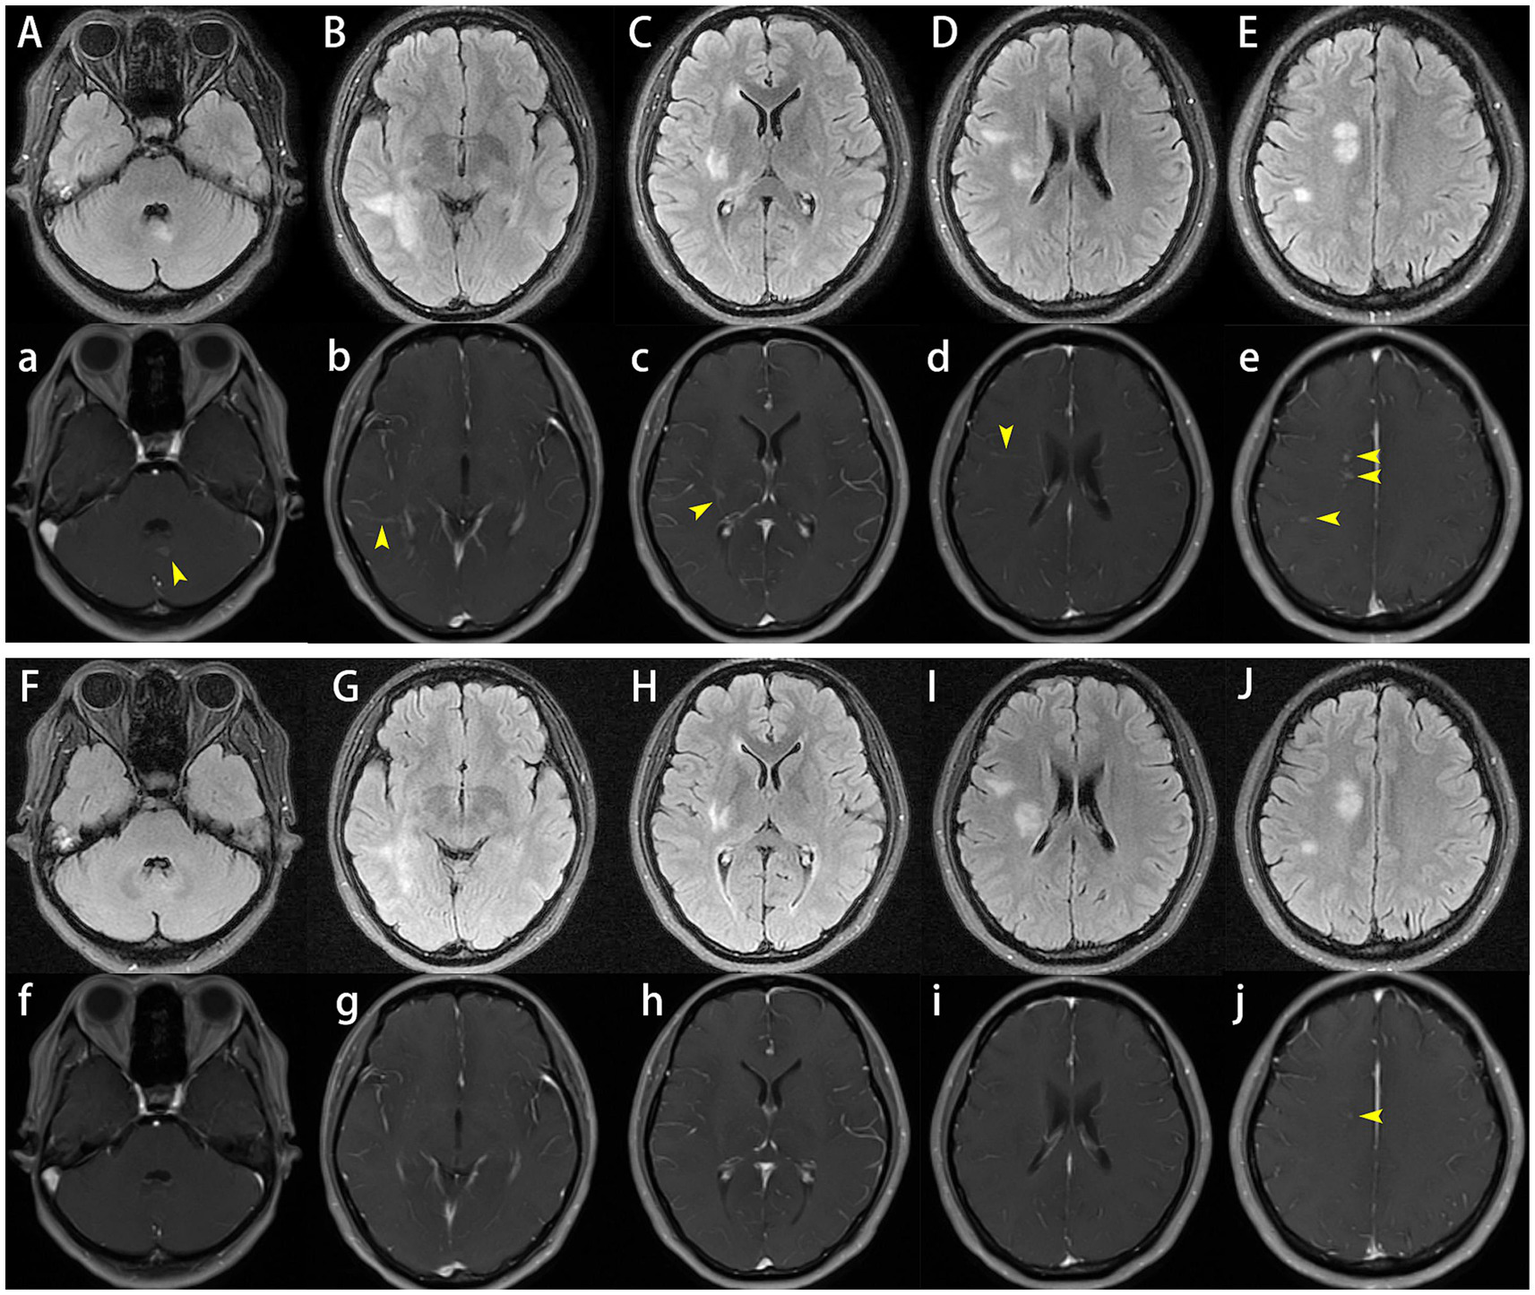

After admission, enhanced MRI of the brain and cervical spinal cord revealed multiple abnormal signals in the intracranial region and cervical spinal cord, with nodular, patchy, or irregular enhancement (Figures 1A–E,a–e, 2A,B). The central vein sign refers to the enhanced venous vascular shadow observed at the center of the lesion, surrounded by abnormal lesional tissue, which was detected on T1-weighted enhanced sequences (Figures 1b–d). Thoracic spinal cord MRI showed no significant abnormalities. Chest CT indicated bilateral minimal pleural effusion.

Figure 1

Cranial plain and enhanced magnetic resonance imaging (MRI). On admission, brain MRI demonstrated multiple abnormal signals in the intracranial region and cervical spinal cord, with nodular, patchy, or irregular enhancement (A–E,a–e), the central vein sign was observed on T1-weighted enhanced sequences (b–d). One month later, follow-up brain MRI showed that reduced lesion size and significant reduction or disappearance of enhancement (F–J,f–j).

The patient was initiated on a therapeutic regimen consisting of oral trimethoprim-sulfamethoxazole (TMP-SMX) 1.44 g every 8 h, intravenous amikacin 0.8 g once daily, and intravenous imipenem-cilastatin sodium 0.5 g every 6 h. Notable gastrointestinal toxicities, including anorexia, nausea, and emesis, necessitated the addition of mosapride, pantoprazole, and vitamin B6, with subsequent resolution of these symptoms. Imipenem-cilastatin sodium was discontinued at 3 weeks, followed by amikacin discontinuation at 6 weeks. One month after therapy initiation, lumbar puncture revealed normal CSF pressure (170 mmH2O), mild leukocytosis at 15 × 106/L (monocyte-predominant), and normal protein and glucose levels. Repeat CSF mNGS yielded negative results, whereas serum MOG-IgG remained persistently positive with stable titers. Serial cranial and cervical spinal MRI demonstrated reduction in lesion size and marked attenuation or resolution of enhancement (Figures 1F–J,f,g, 2C,D). At the 6-week treatment milestone, the regimen was transitioned to oral TMP-SMX in combination with minocycline 100 mg twice daily, with recommendations for continuation for a minimum of 12 months. Complete clinical remission was achieved 2 months following treatment initiation.